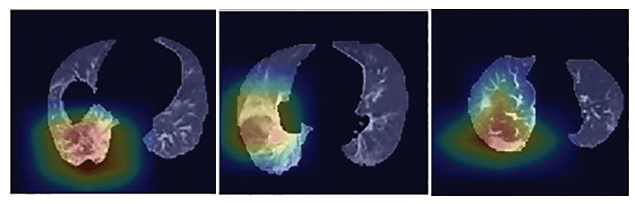

The authors also made Grad-CAM visualizations as a form of model explanation. Grad-CAM is a technique for creating a heatmap that shows where a model is focusing for a particular class. For more details on Grad-CAM see Grad-CAM: Visual Explanations from Deep Networks.

Grad-CAM visualizations. From Li et al.

The authors provide a good commentary on Grad-CAM in their discussion section:

a disadvantage of all deep learning methods is the lack of transparency and interpretability (eg, it is impossible to determine what imaging features are being used to determine the output). While we used a heatmap to visualize the important regions in the scans leading to the decision of the algorithm, heatmaps are still not sufficient to visualize what unique features are used by the model to distinguish between COVID-19 and CAP.